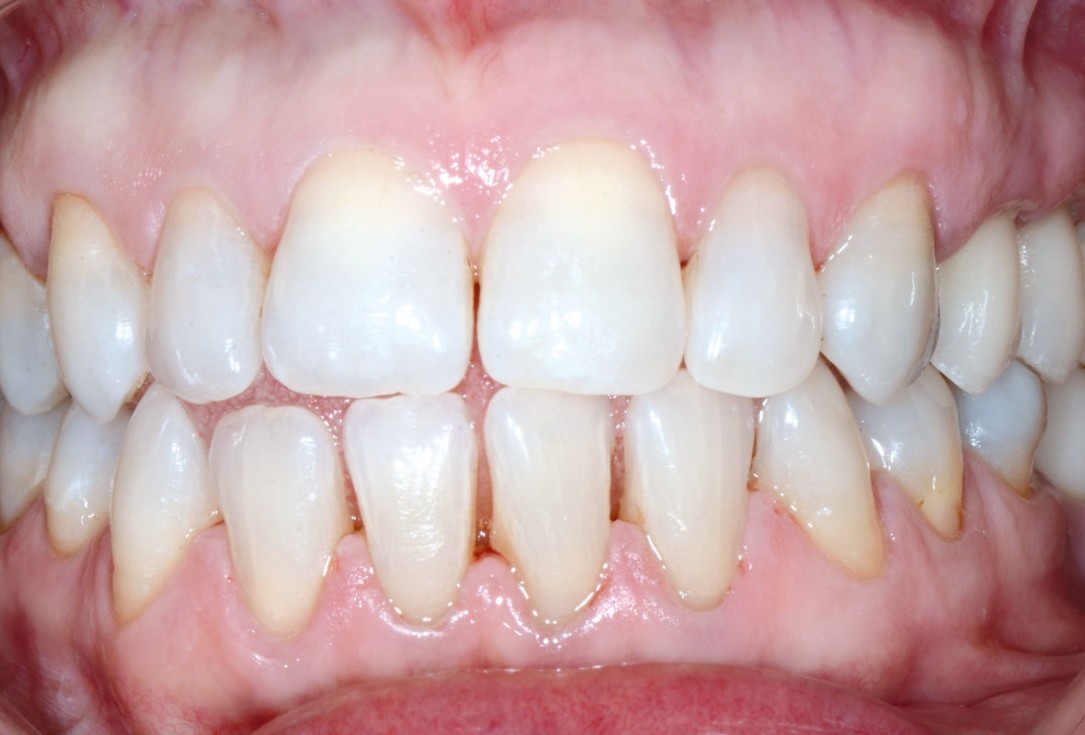

10/13 - Uneventful healing after 6 months

Multiple socket preservation in the maxilla with collacone® max – Dr. D. Jelušić